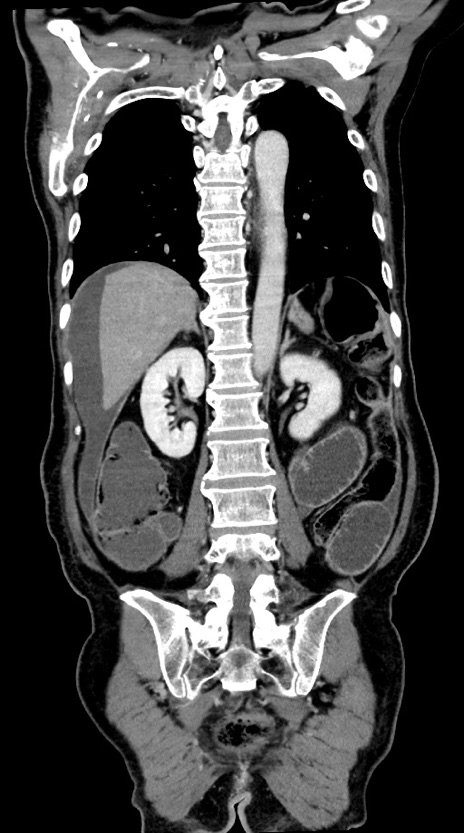

【症例】60歳代男性

【主訴】嘔吐

【現病歴】胃癌にて胃全摘後。食思不振が悪化し、夜中に嘔吐することがある。

【既往歴】胃癌、胃全摘、脾摘、胆摘後

【データ】WBC 5900、CRP 10.56